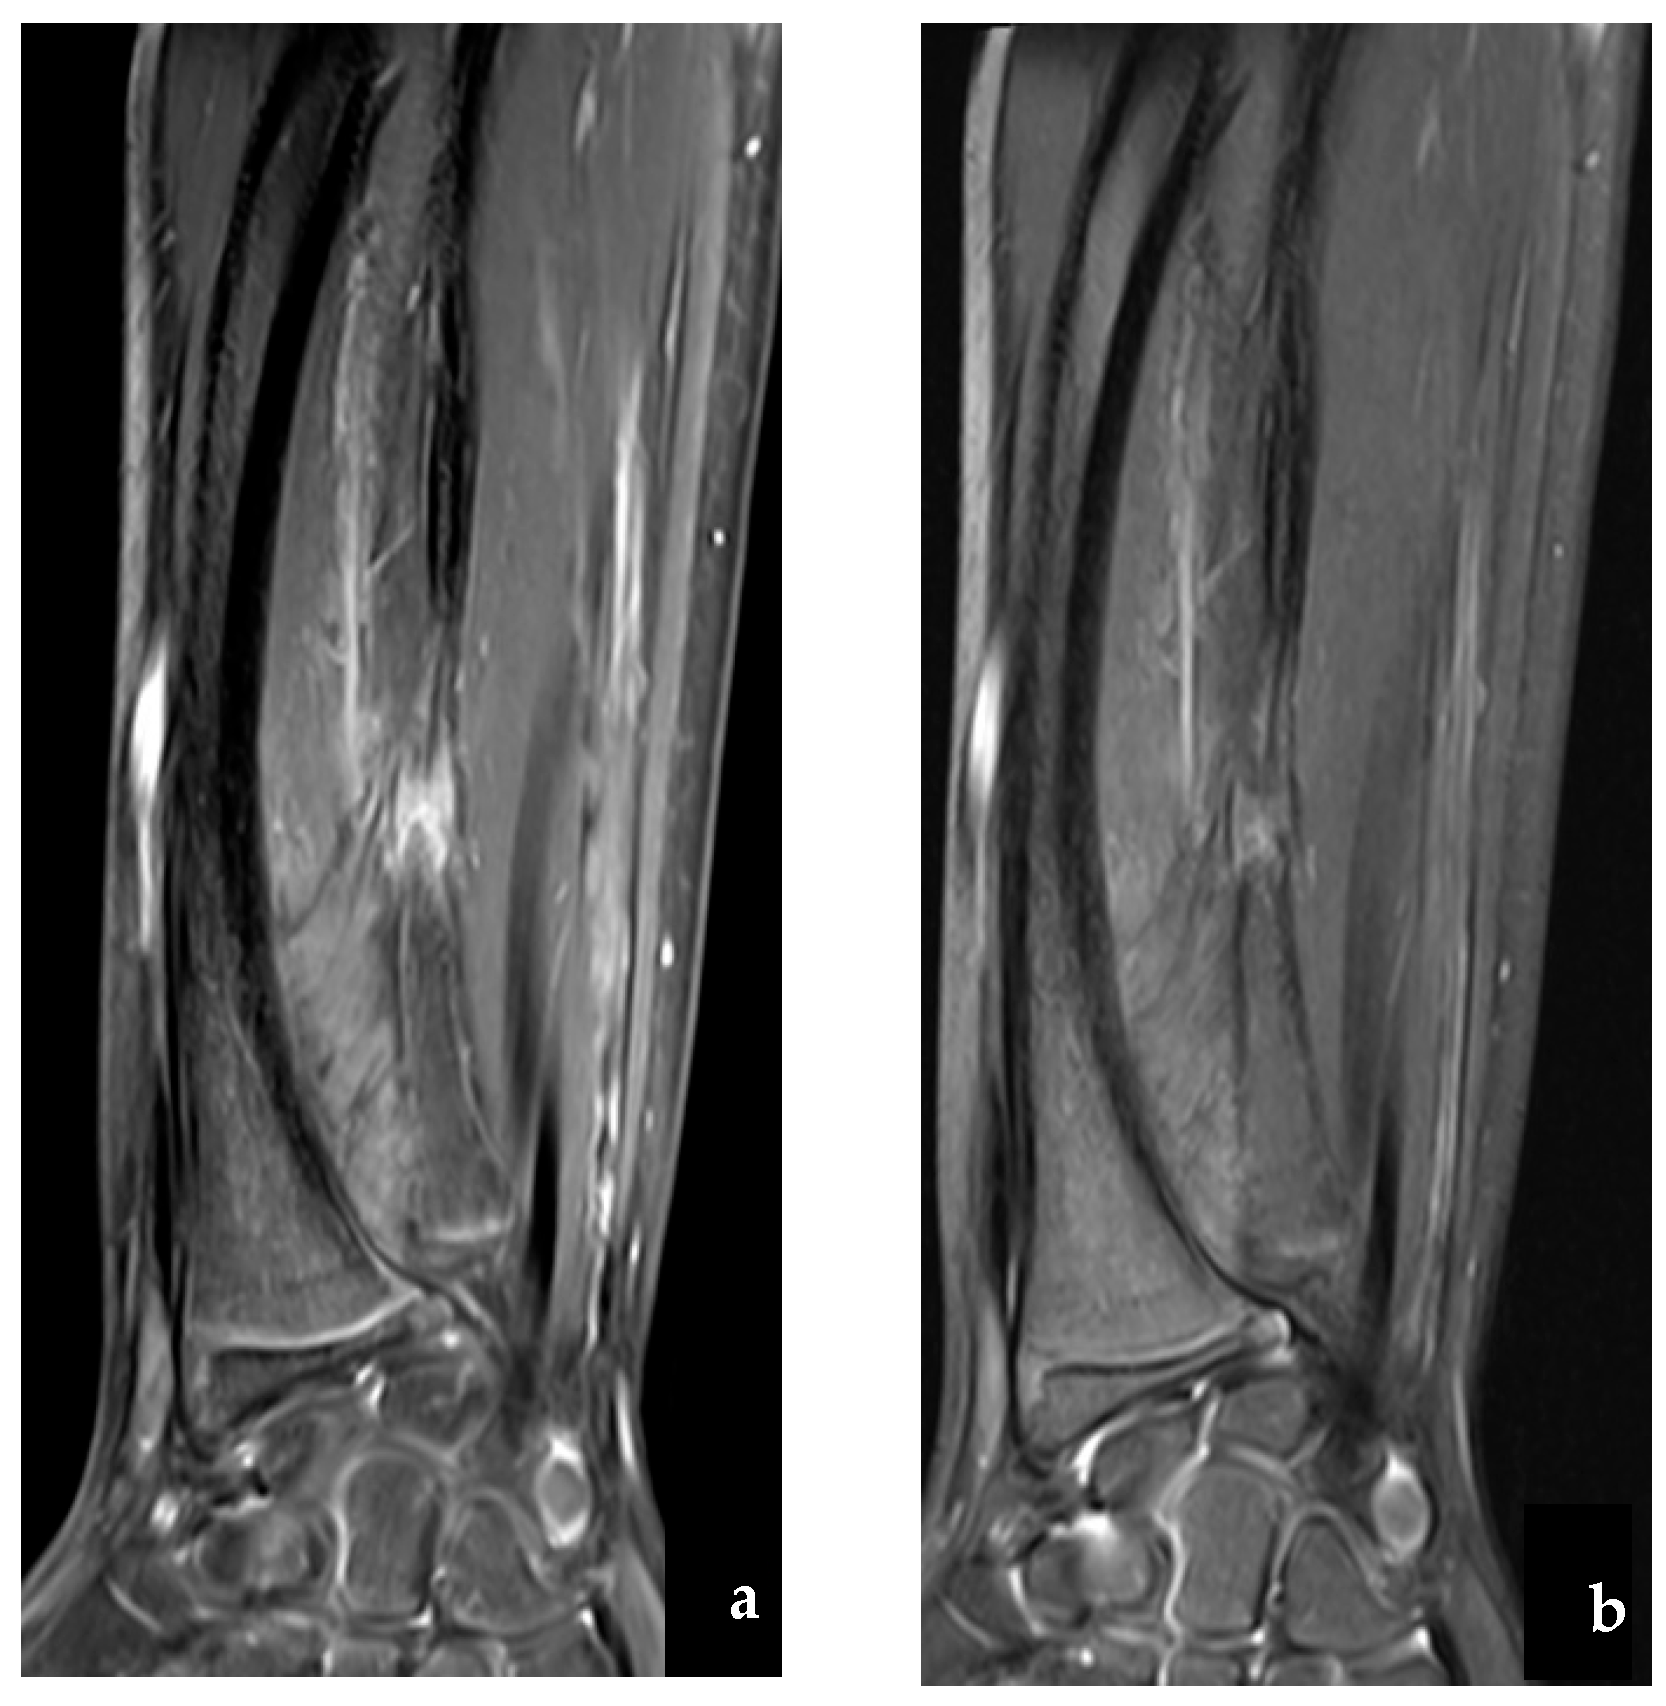

2. Case Report

2.1. Case Report